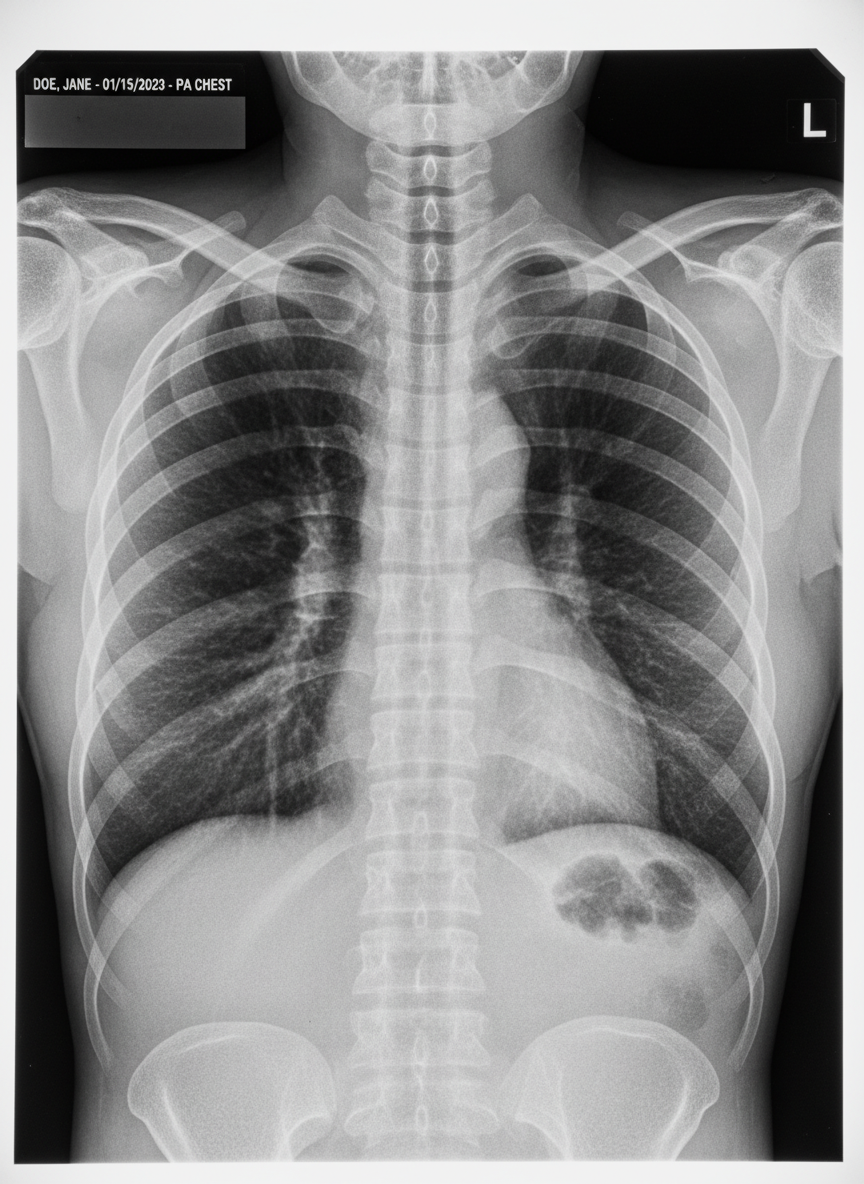

A: 가장 기본적으로는 흉부 X-ray를 촬영하지만, 미세한 기관지확장증이나 초기 병변은 X-ray에 안 보일 수 있습니다. 따라서 객혈 증상이 있다면 저선량 흉부 CT 촬영을 권장합니다.